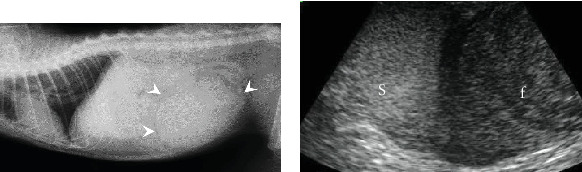

A 6-year-old, intact female cat presented with sudden collapse. Clinical examinations indicated severe regenerative anemia and a large abdominal mass containing fluid. An exploratory laparotomy revealed a large cystic lesion at the cranial end of the right uterine horn. Ovariohysterectomy was performed, and the cat made a full recovery. The cystic lesion contained a blood clot and 102 mL of blood. Histological examination confirmed that the hemorrhagic lesion was located within the fallopian tube. The thickened uterus with severe vasodilation was histologically diagnosed as endometrial hyperplasia with congestion. This is the first reported case of hematosalpinx in a cat, a rare condition previously described in humans.